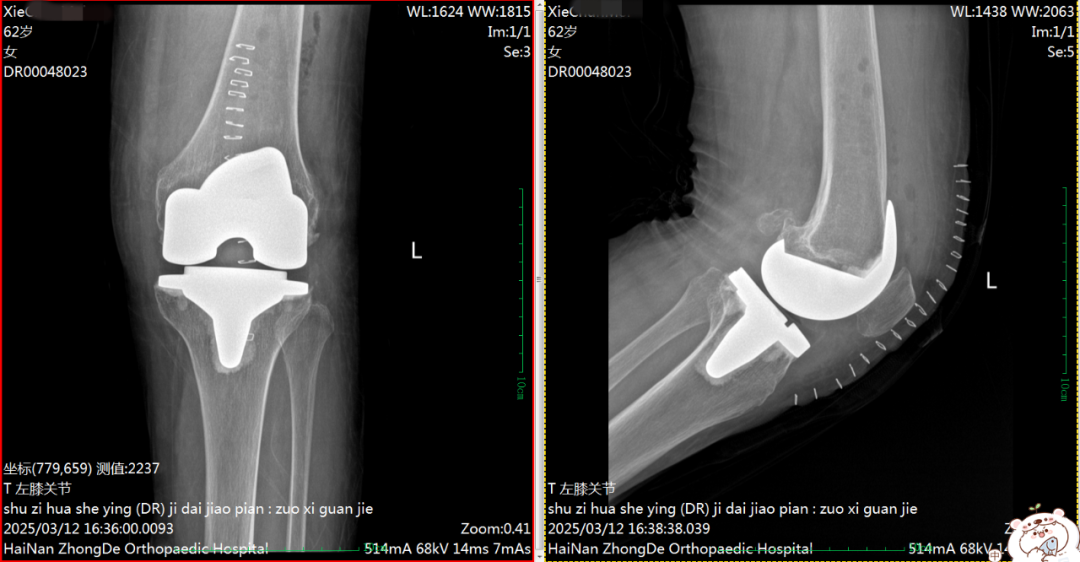

术后DR片

62岁的谢阿姨,5年前左膝出现针刺般酸胀痛感,长期未就诊。入院时,左膝疼痛明显加重伴肿胀、活动受限且呈外翻畸形。术后两周,患者膝关节屈伸功能接近正常水平。

据介绍,相比于内翻膝畸形,外翻畸形的软组织平衡与力线矫正更为困难,手术难度更高,对医护人员的知识储备和手术技术要求也更高。手术的顺利开展,标志着我院在膝关节置换技术方面再上新台阶,付昆教授有力推动我院骨科诊疗技术水平跨越式发展。